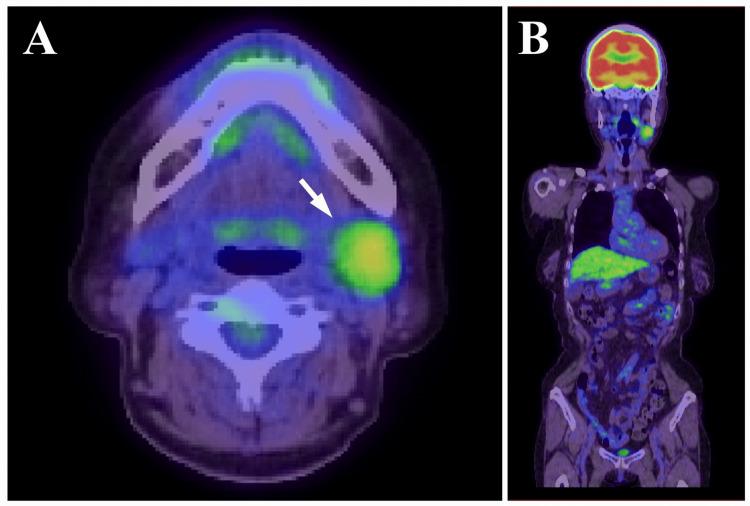

Pleomorphic adenoma (PA) is the most common benign salivary gland tumor, typically arising from the parotid gland. PA of the submandibular gland is relatively uncommon and may present diagnostic challenges, particularly when imaging findings raise suspicion of malignancy. A 66-year-old woman presented with a painless mass in the left submandibular region. Imaging studies including unenhanced computed tomography (CT), magnetic resonance imaging (MRI), ultrasonography (US), and positron emission tomography (PET) revealed a lobulated mass with irregular margins, heterogeneous internal architecture, and partially disrupted capsular structures. PET showed abnormal fluorodeoxyglucose (FDG) accumulation with a maximum standardized uptake value (SUVmax) of 3.70. Based on these findings, malignancies such as adenoid cystic carcinoma or carcinoma ex pleomorphic adenoma (CXPA) were strongly suspected. The tumor was resected under general anesthesia with careful preservation of the capsule and excised en bloc together with the submandibular gland and a portion of the sublingual gland. Histopathological and immunohistochemical analyses revealed no evidence of malignancy, and a final diagnosis of PA was made. This case highlights the diagnostic difficulty of submandibular PA, especially when capsular structures appear ambiguous on imaging. It underscores the limitations of relying solely on imaging modalities and reaffirms the importance of integrating clinical history, imaging, and pathological findings to achieve accurate diagnosis.

多形性腺瘤(PA)是最常见的涎腺良性肿瘤,通常起源于腮腺。下颌下腺的PA相对少见,可能带来诊断挑战,尤其是当影像学表现引发恶性肿瘤怀疑时。一名66岁女性患者,左侧下颌下区出现无痛性肿块。包括平扫计算机断层扫描(CT)、磁共振成像(MRI)、超声检查(US)和正电子发射断层扫描(PET)在内的影像学检查显示,肿块呈分叶状,边缘不规则,内部结构不均匀,包膜结构部分中断。PET显示异常氟脱氧葡萄糖(FDG)摄取,最大标准化摄取值(SUVmax)为3.70。基于这些发现,强烈怀疑为腺样囊性癌或多形性腺瘤恶变(CXPA)等恶性肿瘤。在全身麻醉下切除肿瘤,小心保留包膜,并与下颌下腺及部分舌下腺一并整块切除。组织病理学和免疫组化分析未发现恶性证据,最终诊断为PA。该病例凸显了下颌下腺PA的诊断困难,尤其是当包膜结构在影像学上显示不明确时。它强调了仅依靠影像学检查方法的局限性,并再次肯定了综合临床病史、影像学和病理结果以实现准确诊断的重要性。